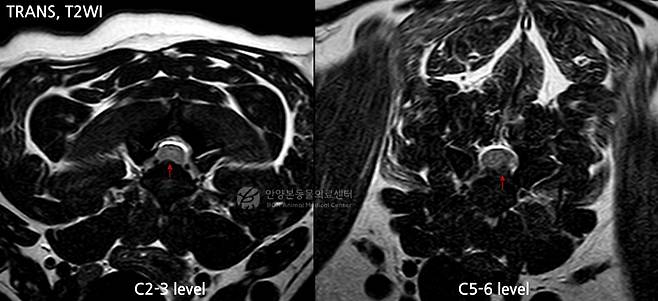

의료진은 원인 확인을 위해 MRI(자기공명영상) 검사를 진행했다. 그 결과 경추 2~3번(C2-3) 부위에서 신경 압박이 확인됐다. 특히 경추 5~6번(C5-6) 부위에서는 디스크가 한쪽으로 심하게 탈출하며 척수를 강하게 누르고 있었다. 의료진은 해당 부위가 급성 마비의 주요 원인으로 판단하고 즉시 수술을 결정했다.

실제 수술 과정에서도 C5-6 부위에서 다량의 탈출한 디스크 물질이 확인됐다. 이를 제거하면서 척수 압박이 해소됐다.